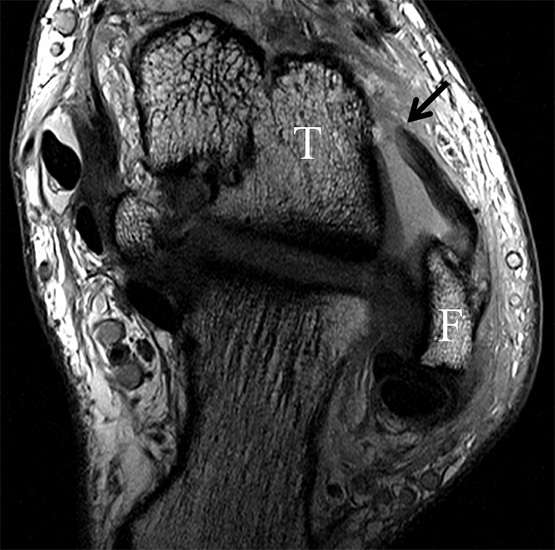

Da also die hintere Syndesmose an der posterioren Tibia inseriert, entspricht eine Fraktur oder Infraktion des hinteren Volkmann`schen Dreiecks funktionell einem knöchernen Ausriss des Ligamentum tibiofibulare posterius (Abb. 18 a und b). Aufgrund der Koinzidenz von Syndesmosenläsionen mit Innenbandverletzungen ist bei der Beurteilung gesondert auf solche zu achten.

b. T2 fs axial. Infraktion des hinteren Volkmann‘schen Dreiecks (schmale, weiße Pfeile). Hier inserierende, intakte, hintere Syndesmose (breite, weiße Pfeile).

Das Ligamentum tibiofibulare posterius (hintere Syndesmose) verläuft flacher und geht nach kranial in das Ligamentum tibiofibulare interosseus und nach kaudal in das Ligamentum intermalleolare posterius über. Letzteres bildet ein artikuläres Labrum zwischen Trochlea und Talus 9.